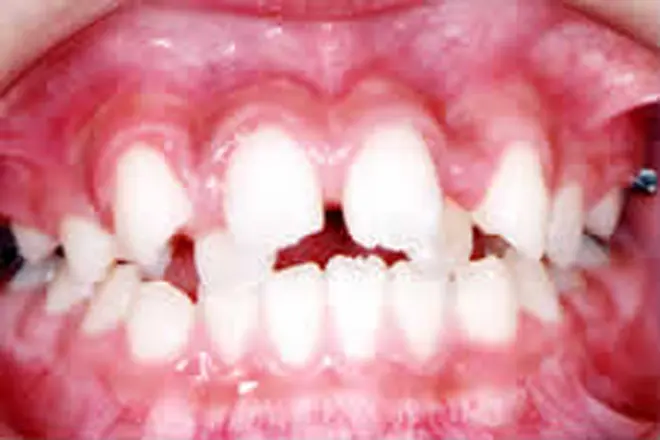

子どもの矯正 治療例4

奥歯が噛み合った状態でも、前歯に隙間ができています。

乳歯が多数あると全体矯正ができないので、歯の裏側に舌突出防止装置を付けました。これにより、舌が前に出る圧力を押さえました。

噛み合わせが整い、デコボコも解消されました。